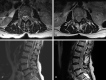

Stem cell therapy can present clinicians with challenging clinical scenarios, as access to such treatments outpaces the research into their efficacy and safety due to the burgeoning trend of international travel to acquire stem cell therapy, or "stem cell tourism." Treatment of neurologic conditions remains an enticing potential application of stem cell therapy, often administered intrathecally. In response to such therapy, multiple adverse events have been described in the literature, including neoplasms, demyelinating disease, and seizures, among others. We present a case of symptomatic inflammatory cauda equina nerve root hypertrophy due to intrathecal stem cell infusion, representing a rare but significant complication.